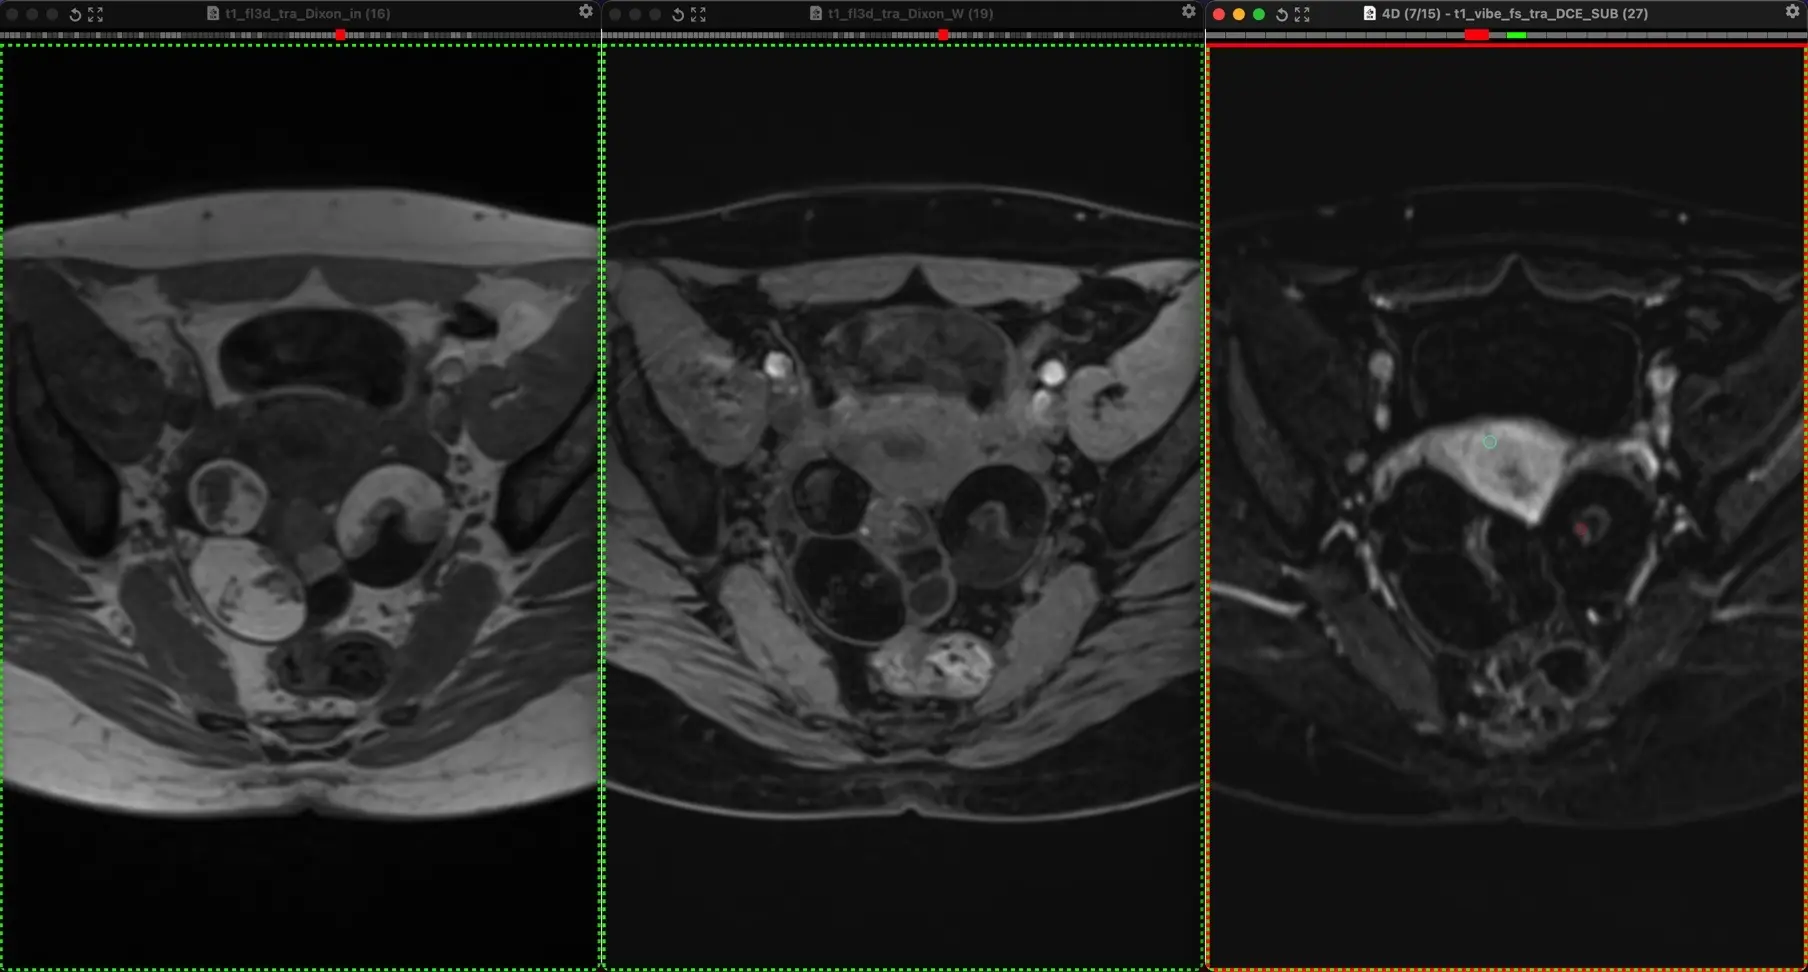

Классные тератомы. 30 лет.

В ОРАЦ есть интересный момент: когда речь о тератоме, то надо оценить, есть ли значительное количество ткани, накапливающей контраст. Субъективная вещь. Один сочтёт, что значительное, другой сочтёт, что не значительное. Но в первом случае это будет четвёртая категория и опухоли надо удалять, а во втором случае это будет вторая категория, и можно просто спокойно понаблюдать. Только что переубедил коллегу написать двойку вместо четвёрки по этим картинкам.

Кривую показываю на всякий случай, она на присвоение категории в данном случае не влияет, но дополнительно успокаивает, что ли. А зубчатость её объясняется тем, что исходные изображения и изображения после субтракции представляют собой одну серию, а вручную их разделять мне было лень. На информативность кривой это никак не влияет.

Видно, что в миометрии контраст накапливается гораздо быстрее и гораздо сильнее. То есть, если бы это на что-то влияло, то эту кривую надо было бы расценить, как кривую низкого риска.